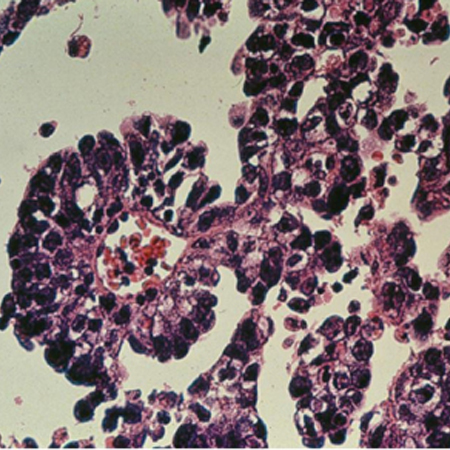

O diagnóstico definitivo do câncer de ovário é baseado na histopatologia.[90][Figure caption and citation for the preceding image starts]: Visualização microscópica de câncer de ovárioDo acervo de Justin C. Chura, MD, Cancer Treatment Centers of America, Filadélfia, PA [Citation ends].

Geralmente, é necessária a remoção cirúrgica do ovário afetado para o diagnóstico histológico. A cirurgia é também usada para estadiamento e citorredução do tumor.

crescimento destrutivo infiltrante mais bem demonstrado por grupos de células desorganizadas, geralmente com desmoplasia